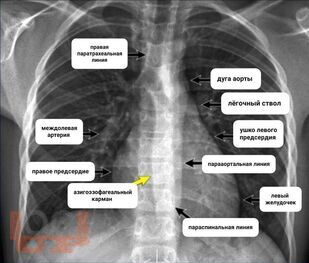

Рентгеноанатомия органов грудной клетки

В учебном пособии представлена информация о нормальной рентгеновской анатомии органов грудной полости, вариантной анатомии, наиболее частых аномалиях развития, скиалогии, алгоритме описания рентгенограмм и основных требованиях по оформлению протокола рентгенологического исследования.